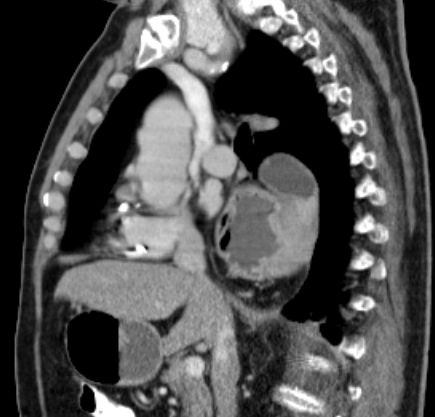

Doppelkarzinom 81-jähriger Patient, der vor 50 Jahren eine 2/3-Resektion des Magens wegen Ulkus hatte.

Vor 4 Jahre Rektum-Karzinom: Radiochemotherapie, Radikaloperation.

Jetzt Einweisung wegen eines Plattenepthelkarzinoms des Magens.

Endoskopie:2 Tumoren. 1.Ösophaguskarzinom mit teilweiser Stenosierung (Plattenepithelkarzinom).

Gesichertes Magenkarzinom ohne Stenosierung (Adenokarzinom).